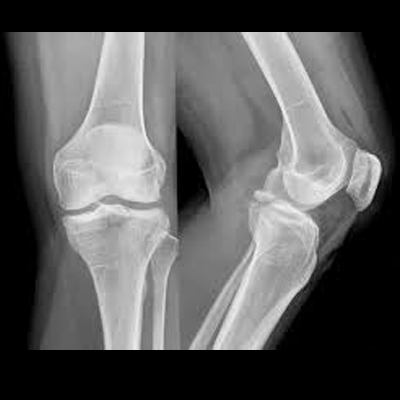

X-rays are primarily used in the medical and dental field. Some of the more common X-rays are done for broken bones and fractures, swallowed items, damage to bones from arthritis, and lung infections. X-rays are also used in a CT scanner, or computed tomography. This modality uses multiple X-rays during one scan, to give a layer-by-layer image. X-rays are also being used in non-medical areas, like airport security and by NASA in outer space.